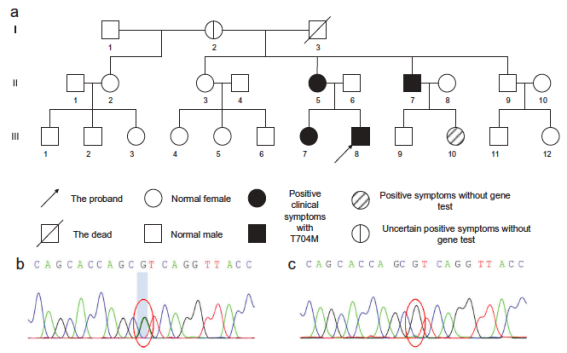

其中一个家系中部分成员基因分析考虑SCN4A基因(T704M)为其致病突变����,其长时程运动试验提示患者于常温所致先天性副肌强直合并高钾型周期性麻痹����。